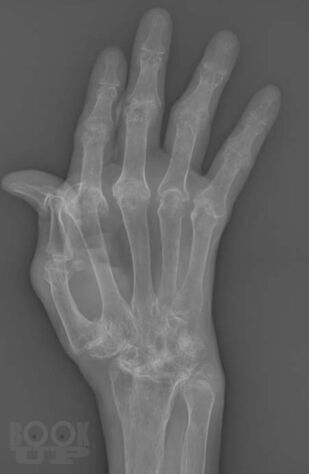

В учебном пособии представлены основные сведения о ревматологических заболеваниях, которые протекают с поражением суставов кисти, подробно изложена их рентгенологическая семиотика, описаны диагностические возможности других методов лучевой диагностики, таких как ультразвуковая диагностика, магнитно-резонансная и компьютерная томография. Особое внимание уделено дифференциальной диагностике заболеваний кисти.